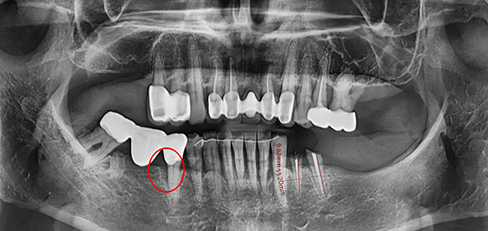

잇몸속 치아를 싸고 있는 치조골이 2/3 정도 소실되면

임플란트를 하고 그보다 치조골 손실이 적으면 비수술식

잇몸 치료를 통하여 자연치아를 최대한 살리려고 노력합니다.